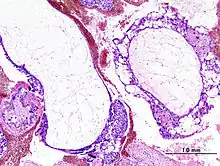

Histopathologic image of hydatidiform mole (complete type). H & E stain. -

A hydatidiform mole is a pregnancy/conceptus in which the placenta contains grapelike vesicles (small sacs) that are usually visible to the naked eye. The vesicles arise by distention of the chorionic villi by fluid. When inspected under the microscope, hyperplasia of the trophoblastic tissue is noted. If left untreated, a hydatidiform mole will almost always end as a spontaneous abortion (miscarriage).

Based on morphology, hydatidiform moles can be divided into two types: in complete moles, all the chorionic villi are vesicular, and no sign of embryonic or fetal development is present. In partial moles some villi are vesicular, whereas others appear more normal, and embryonic/fetal development may be seen but the fetus is always malformed and is never viable.

The diagnosis is strongly suggested by ultrasound (sonogram), but definitive diagnosis requires histopathological examination. On ultrasound, the mole resembles a bunch of grapes ("cluster of grapes" or "honeycombed uterus" or "snow-storm").[14] There is increased trophoblast proliferation and enlarging of the chorionic villi, and angiogenesis in the trophoblasts is impaired.[15]